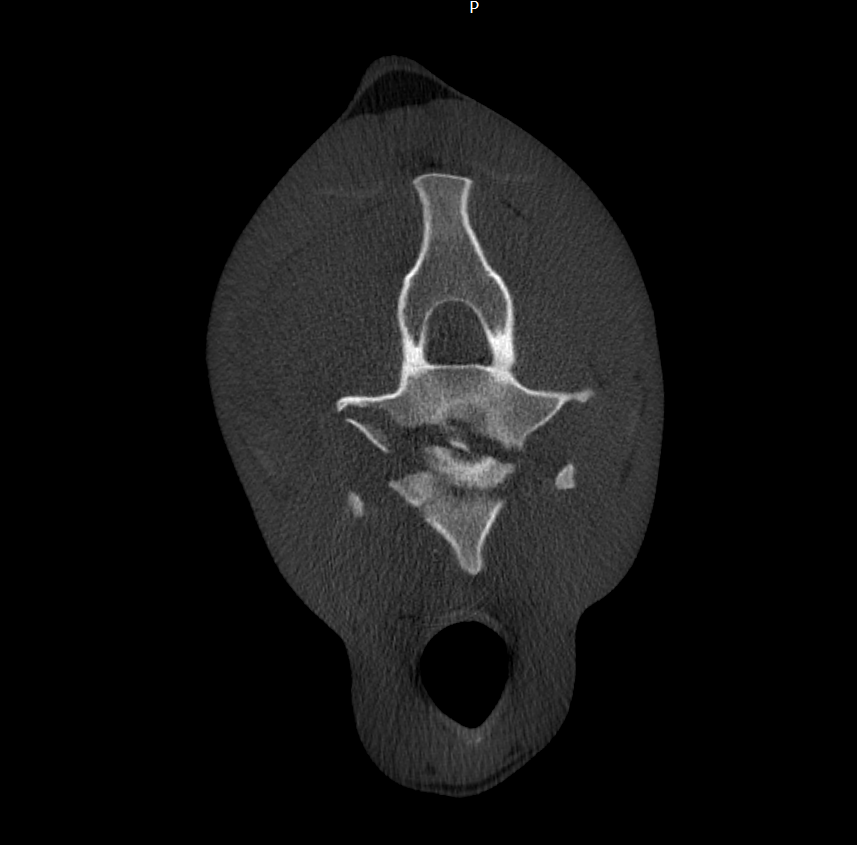

Cross-sectional medical scan image of a human spine viewed from below

CT Tenogram